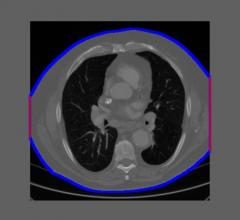

One of the main benefits of a radiation dose management system is the possibility to automatically generate alerts when the dose exceeds certain thresholds. These dose thresholds are mainly based on national Diagnostic Reference Levels (DRLs), which are defined for a standard-sized patient. An advanced dose management system offers the possibility to automatically select the group of patients by defining a patient size range in terms of weight, effective diameter or Water Equivalent Diameter (WED). As weight is not always filled in, WED, an attenuation-based metric, has become the favourite parameter to indicate patient size. But how accurately is WED calculated? Are we sure that our group of standard-sized patients does not include patients with wrong size calculation? Especially when everything happens automatically, how can we know that a high dose alert does not indicate a bigger patient for whom the size was not correctly calculated?